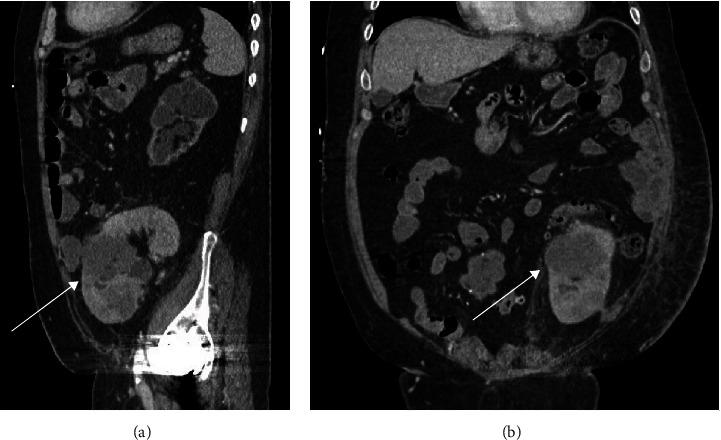

Cancer is a significant cause of morbidity and mortality in recipients of renal transplantation. The vast majority develop from recipient origins, whereas donor-derived malignancies are exceedingly rare. We report 2 cases of poorly differentiated donor-derived urothelial carcinoma (UC) in renal transplantation recipients. The first patient underwent a living-related-donor renal transplantation 24 years prior and presented with back pain, hematuria, and rising creatinine and was found to have a 14 cm mass in the renal allograft with regional lymphadenopathy and liver metastases. Pathology showed UC with small-cell differentiation. The second patient presented with hematuria and rising creatinine and was initially found to have muscle invasive bladder cancer seven years after a deceased donor renal transplantation. Nine months after radical cystectomy, a large 9 cm mass was found on his allograft, for which radical nephrectomy and excision of prior ileal conduit was performed. Pathology showed UC with sarcomatoid differentiation. Short tandem repeat (STR) genotyping confirmed donor-derived origins. Both patient tumors expressed PD-L1 suggesting an additional therapeutic avenue for these rare tumors.

癌症是肾移植受者发病和死亡的重要原因。绝大多数癌症起源于受者,而供体来源的恶性肿瘤极为罕见。我们报告了2例肾移植受者中低分化供体来源的尿路上皮癌(UC)病例。首例患者24年前接受了亲属活体供肾移植,出现背痛、血尿和肌酐升高,在移植肾中发现一个14厘米的肿块,伴有区域淋巴结病和肝转移。病理显示为小细胞分化的UC。第二例患者出现血尿和肌酐升高,在接受尸体供肾移植7年后最初被发现患有肌层浸润性膀胱癌。根治性膀胱切除术后9个月,在其移植肾中发现一个9厘米的大肿块,为此进行了根治性肾切除术和先前回肠导管切除术。病理显示为肉瘤样分化的UC。短串联重复序列(STR)基因分型证实了供体来源。两名患者的肿瘤均表达PD-L1,提示这些罕见肿瘤有额外的治疗途径。